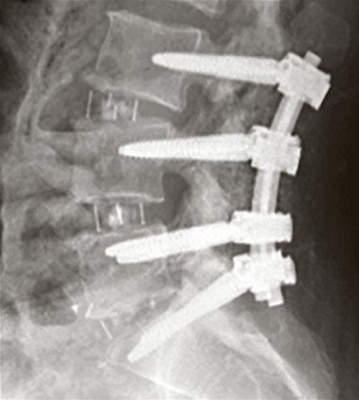

Vordere Wirbelkörperabstützung mit einem Platzhalter und hintere Fixation mit Schrauben.

Vor allem entzündliche Veränderungen können die Lendenwirbelsäule destabilisieren und in der Folge Rücken- und Beinschmerzen hervorrufen. Ziel des Eingriffs ist es deshalb, die dafür ursächlichen Bandscheiben bzw. Bewegungssegmente zu stabilisieren und dadurch die Schmerzen bestmöglich zu lindern oder gar zu beseitigen. Neu an der Lateral-Access-Methode ist der seitliche, von der Flanke geführte operative Zugang zur Lendenwirbelsäule. Dabei wird über einen Schnitt von 3 bis 4 cm über der Flanke (links oder rechts) der muskel- und bindegewebeschonende Zugang direkt zur Wirbelsäule aufgesucht. Durch ein röhrenförmiges Instrument (Spreizer) kann dann in der Tiefe sorgfältig und zielgerichtet an der Bandscheibe bzw. Lendenwirbelsäule gearbeitet werden. Dabei wird die defekte Bandscheibe entfernt und durch einen grossflächigen Platzhalter ersetzt. Dieser Platzhalter wird mit Knochengewebe gefüllt, damit ein solider Knochendurchbau die beiden angrenzenden Wirbelkörper verbindet (Fusion). Zur Erhöhung der primären Stabilität wird oftmals durch den gleichen Operationszugang eine die Wirbelkörper verbindende Platte eingebracht und mit Schrauben fixiert. In einigen Fällen werden die stabilisierenden Schrauben durch minimalinvasive Zugänge über den Rücken eingebracht (Pedikelschrauben-System).